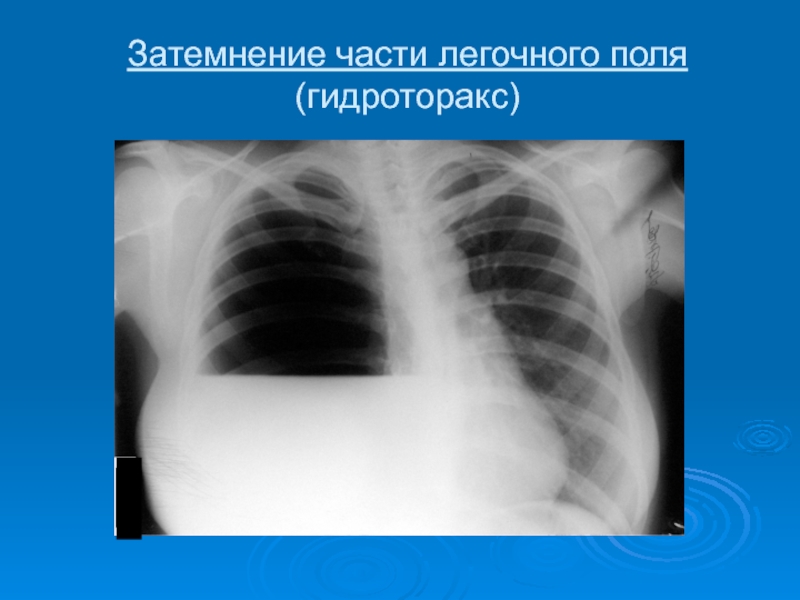

Слайд 39Затемнение части легочного поля (гидроторакс)

Затемнение части легочного поля (гидроторакс)